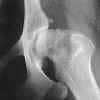

Osteoarthritis in dogs is diagnosed through a physical exam and imaging.

Radiographs (X-ray)